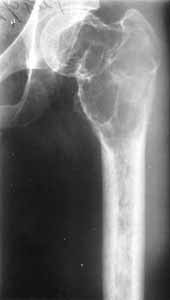

Tumour of upper/third of hip at the age of twenty four.